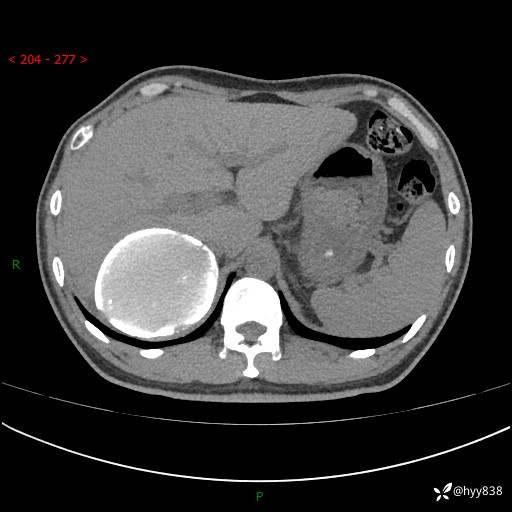

性别:男

年龄:50岁

简要病史:夜尿增多半月,发现肾功能异常1天,超声发现腹膜后占位

腹部CT平扫+增强